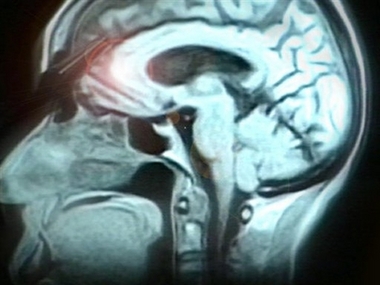

When the monkeys voluntarily concentrated, the so-called executive center in

the front of the brain - the prefrontal cortex - was in charge. But when

something distracting grabbed the monkeys' attention, that signal originated in

the parietal cortex, toward the back of the brain.

The electrical activity in these two areas began vibrating in synchrony as

they signaled each other. But it was at different frequencies, almost like being

at different spots on the radio dial.

Sustaining concentration involved lower-frequency neuron activity.

Distraction occurred at higher frequencies. So, Miller concluded, scientists one